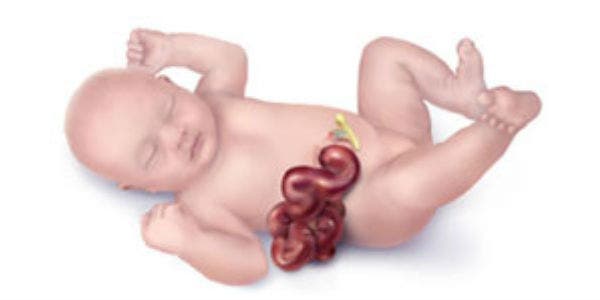

Les confirmaron que Noah vendría con una afección llamada gastrosquisis, es decir que nacería con los intestinos afuera

El pequeño Noah Lemmon nació un mes antes de lo previsto, el pasado 28 de junio, tal como predijeron los médicos, con sus órganos sobresaliendo. Por lo que debía ser llevado de inmediato a la UCI para ser sometido a una cirugía de emergencia.

Es una rara condición que sucede en 1 de cada 3.000 bebés nacidos cada año, y que afecta principalmente a madres jóvenes, pero todavía su causa es desconocida.

Se da porque la pared abdominal no se forma por completo, por lo que los intestinos del bebé se desarrollan afuera y están expuestos al aire cuando el niño nace. Lo que implica infecciones potencialmente mortales.